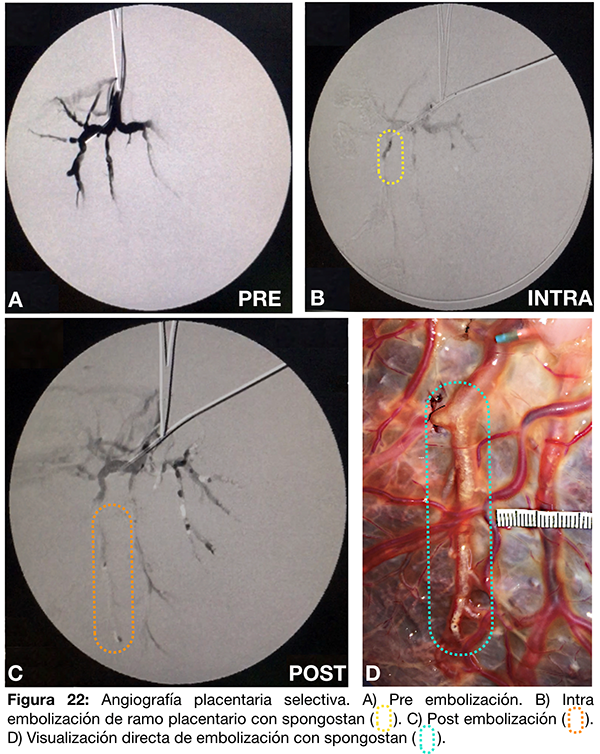

IV- Embolización de ramo distal con spongostan.

Se cateteriza un vaso arterial placentario con un catéter guía 6F y se inyecta contraste diluido al 70% (fig. 22 A). Se realiza un mapa seco (road mapping sin inyección de contraste previa) y se embolizan desde el catéter guía en forma progresiva los ramos distales utilizando Spongostan® fragmentado en una jeringa de 5ml con contraste al 50% (fig. 22 B-C). Finalmente se observa en forma directa el material de embolización intraarterial (fig. 22 D).